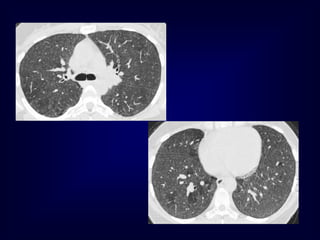

A 27-year-old man is referred to you for evaluation of an

abnormal chest radiograph. About 5 months ago, he consulted

a doctor because of excessive thirst. Evaluation resulted in the

diagnosis of diabetes insipidus, which responded favorably to

desmopressin administered nasally. Recently, he started to

notice shortness of breath when climbing stairs, and a chest

radiograph was obtained.

•Patient history reveals significant tobacco smoking, up to two

packs daily, for at least 14 years. The patient noticed the

shortness of breath for at least 2 years, and recently, he noted

a point of tenderness over the chest wall, lateral to the

posterior axillary line on the left.

•Oxygen saturation is 94% while breathing room air, and the

rest of his vital signs were normal. Auscultation reveals only

rare crackles without prolongation of the expiratory phase.

There is a point of tenderness over the left sixth and seventh

ribs in the posterior axillary line, and a chest CT scan is

obtained.

Langerhans Cell Histiocytosis

HRCT Findings

Small peribronchiolar nodules (1-5mm)

Thin-walled cysts (< 1cm),

Bizarre and confluent

Ground glass opacities

Late signs: irreversible / parenchymal fibrosis

Honey comb lung, septal thickening,

bronchiectasis

1 year later

Peribronchiolar Nodules Cavitating nodules and cysts

Langerhans Cell Histiozytosis

Key Features

Upper lobe predominance

Combination of cysts and noduli

Characteristic stages

Increased Lung volume

Sparing of costophrenic angle